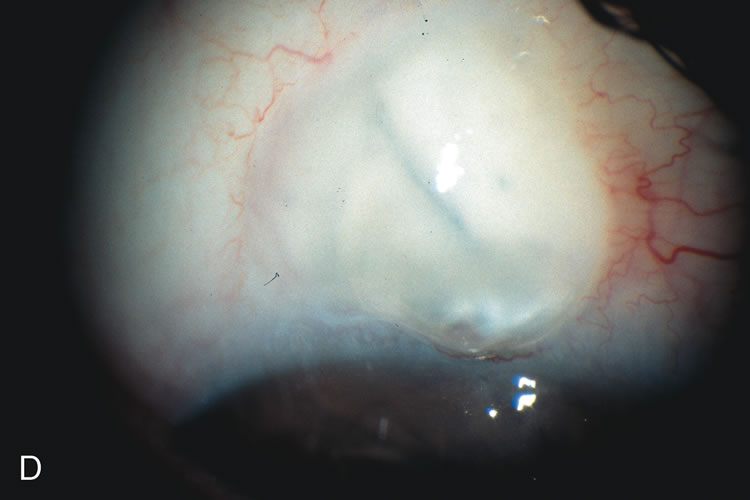

Fig. 3. Partial bleb failure following clear corneal phacoemulsification with foldable IOL. A. Preoperative bleb appearance prior to temporal lens extraction. Preoperative IOP was 12 mm Hg on no antiglaucoma medications. Time from 5-FU trabeculectomy surgery to lens extraction was one year. B. Bleb appearance 2 months after clear corneal cataract surgery with topical anesthesia. Following lens extraction, increased vascularity was noted along with decreased size of the filtering bleb. IOP increased to 20 mm Hg as early as 2 weeks after surgery, necessitating topical antiglaucoma therapy. C. High magnification view of bleb before lens extraction demonstrates diffuse pale bleb. D. High magnification view of bleb 2 months after surgery. There are vessels surrounding the nasal side of the bleb and the overall bleb size is smaller.